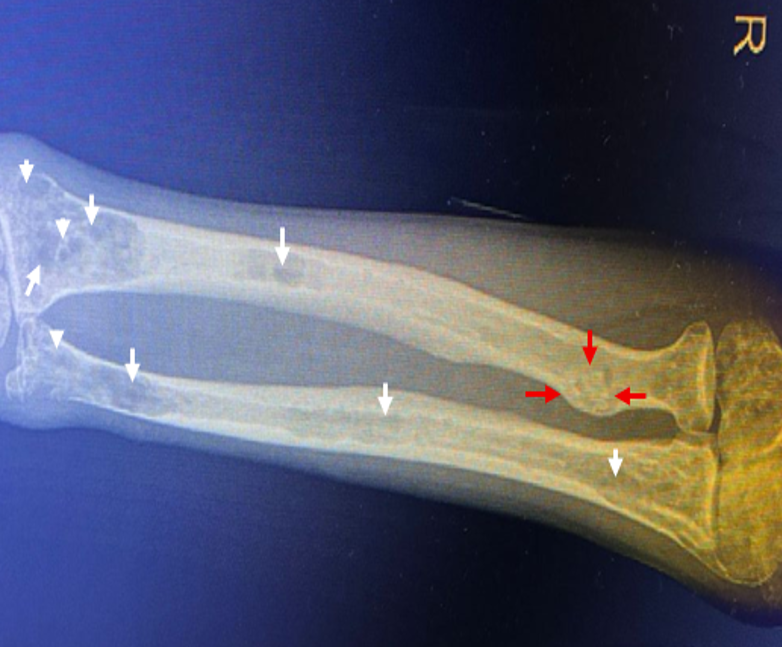

Femoral Shaft Fracture with Popliteal Artery Injury: A Case Report of a Gunshot Wound

Noémie Fourcroy Maillard, Flávia Nunes Benicio de Souza, João Alexandre Ranzeiro de Bragança dos Santos, Julia Habibe de Souza, Manuella Santos de Rezende, Vinicius Macário Mendes, José Antônio Vieira da Silva Calsoni, Frederico do Amaral Bahia, Ana Paula de Carvalho Miranda Rosati, Luis Fernando Rosati